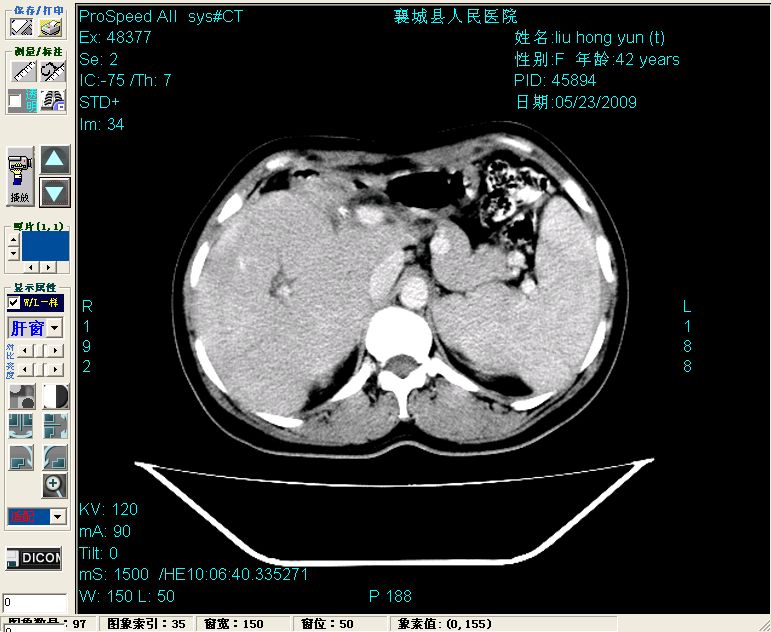

平扫:

增强:

平扫左肝外叶体积显著减小,左肝外叶见多房囊性低密度区,左肝实质及右肝前叶浅表实质呈低密度改变,左肝及右肝前叶胆管扩张,脾大

增强动脉期前述低密度区轻度早其强化,门脉期强化程度显著增高,延期扫描强化程度下降,但仍为相对高密度影

胰头部见结节状高密度影,其前方略可分辨扩强胆部管,平扫到增强始终有,但现在尚难与胃肠造影剂鉴别.

结合病史考虑,1现在引起黄疸体征的原因应该是胆总管胰段结石阻塞,建议局部胃肠造影剂排空后复查.

2左肝及右肝前叶表现考虑胆囊摘除术后所致的肝动门脉瘘形成,慢性纤维组织炎性增生.不完全除外左肝胆管细胞癌

3脾大,可能与动门脉瘘所致门脉高压有关